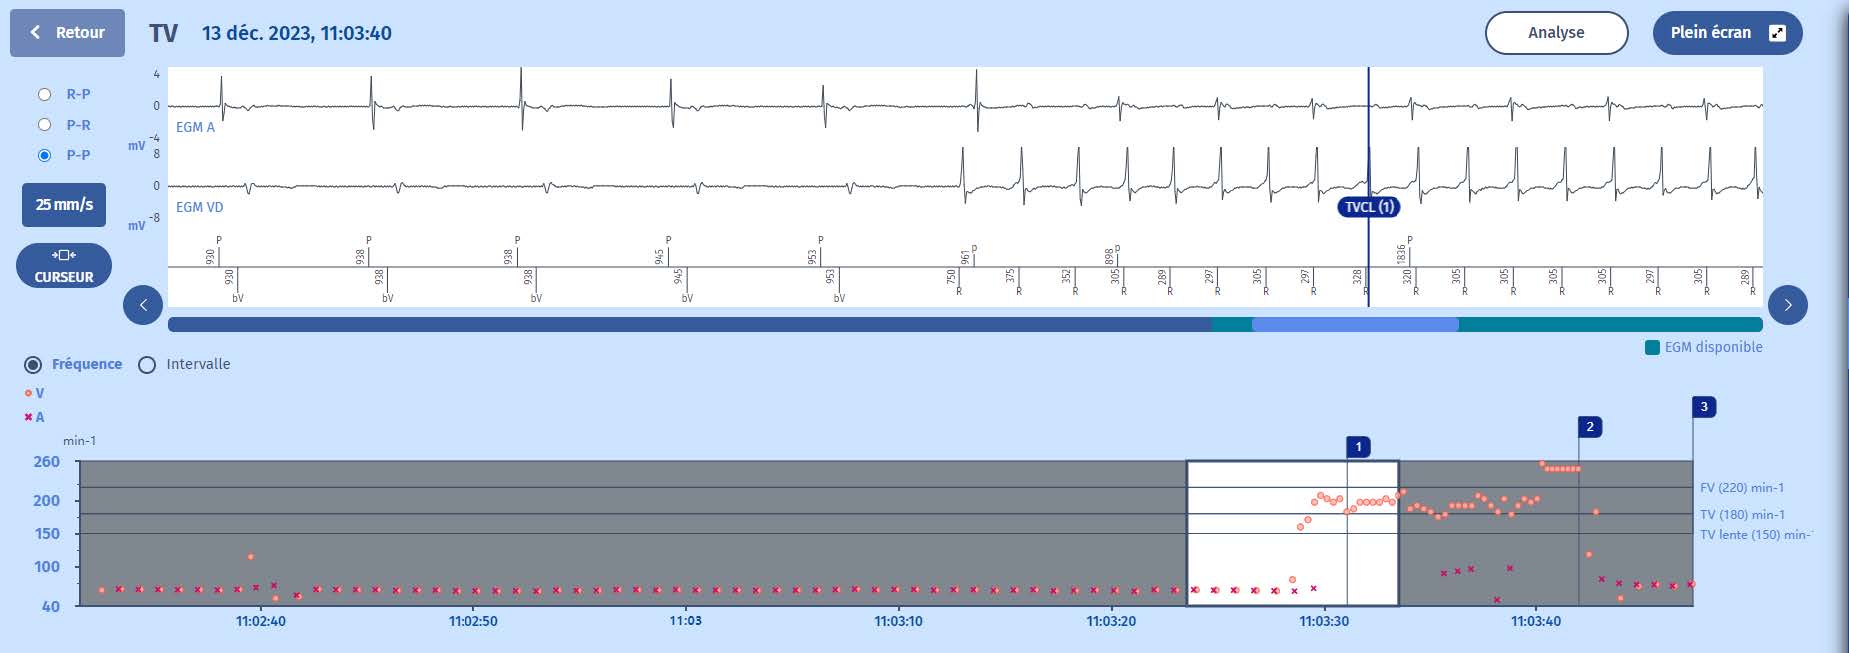

Tracés : Le tracé en haut est l'électrogramme auriculaire, en dessous, l'électrogramme ventriculaire, et enfin, en bas, les marqueurs auriculaires au-dessus de la ligne et les marqueurs

ventriculaires en dessous, ainsi que les intervalles de temps.

Tachogramme

1 Le rythme est sinusal avec resynchronisation biventriculaire.

2 La tachycardie ventriculaire commence dans la zone TV (points orange), tandis que le rythme auriculaire reste lent (croix violettes (x)).

3 Une SAT est délivrée avec un retour au rythme sinusal dans la zone lente.

1 Le rythme est sinusal avec une stimulation biventriculaire synchronisée.

2 Début de la tachycardie ventriculaire. Le premier cycle de tachycardie (750 ms) est en dehors de la zone de tachycardie (400 ms). Pour le défibrillateur, la tachycardie

commence aux cycles suivants qui sont dans la zone de tachycardie ventriculaire ((375 ms, 352 ms 180/min). Le critère des 6 cycles sur 8 dans la zone de TV est rempli. Le

rythme ventriculaire est stable et il y a une dissociation atrio-ventriculaire (plus de signaux ventriculaires qu'auriculaires). Le marqueur est : 1 (TVLC). La phase de

la persistance commence.

3 Après 30 cycles de persistance pendant lesquels tous les cycles sont dans la zone deTV, une salve de stimulation anti-tachycardique est initiée pour 8 cycles fixes (c'est la

première thérapie programmée dans cette zone), indiquée par le second marqueur :ATP (2).

4 L'ATP est efficace pour mettre fin à la tachycardie, et après 6 cycles lents (et une ESV à328 ms), l'épisode est terminé (étiquette : Rythme lent)